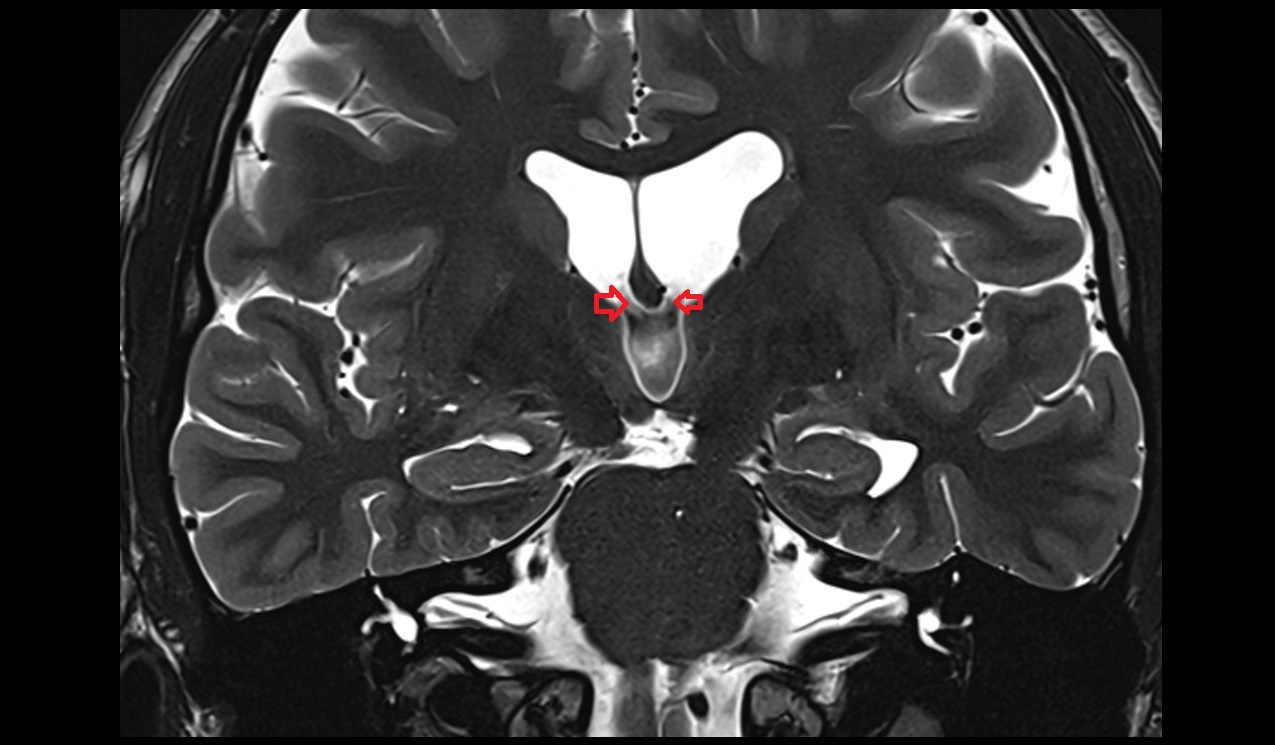

- Hippocampus

- Body of hippocampus

- Head of hippocampus

- Tail of hippocampus